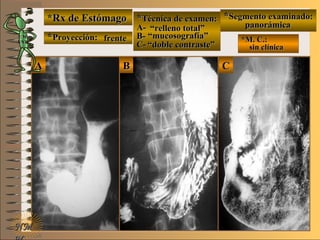

*Rx de Estómago*Rx de Estómago

**Proyección:Proyección:

**Técnica de examen:Técnica de examen:

**Segmento examinado:Segmento examinado:

*M. C.:*M. C.:

epigastralgiaepigastralgia

melenamelena

NMNM

detalledetalle

frentefrente

““doble contraste”doble contraste”

antro gástricoantro gástrico

A-A-El examen es normal o patológico?El examen es normal o patológico?

Examen patológico de estómago con técnica deExamen patológico de estómago con técnica de

doble contraste en proyección de frentedoble contraste en proyección de frente

B-B-La patología es congénita o adquirida?La patología es congénita o adquirida?

Patología adquiridaPatología adquirida

C-C- Dicha patología es orgánica, funcional o mixta?Dicha patología es orgánica, funcional o mixta?

Patología adquirida orgánicaPatología adquirida orgánica

D-D-La misma es neoplásica o no neoplásica?La misma es neoplásica o no neoplásica?

Patología adquirida orgánica no neoplásicaPatología adquirida orgánica no neoplásica

E-E-Puede describir la o las imágenes patológicas?Puede describir la o las imágenes patológicas?

Se identifican en antro gástrico múltiplesSe identifican en antro gástrico múltiples imáge-imáge-

nes mixtasnes mixtas UNTUNT : elevado (inflamación) y: elevado (inflamación) y

deprimidas (erosión) focales compatibles condeprimidas (erosión) focales compatibles con

una gastritis madura completauna gastritis madura completa

**Proyección: frenteProyección: frente

imágimág.. elevado-deprimidaelevado-deprimidavolvervolver